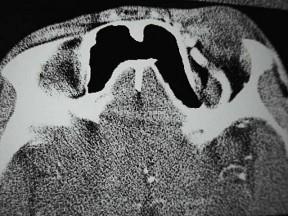

问题 男,44岁,车祸伤及右侧眉弓和头部,当时右眼上、下睑青紫淤血,半月后右眼球结膜高度水肿视力下降,右眼球突出,CT检查如图,最可能的诊断为()

选项 A.眶内静脉曲张 B.颈内动脉海绵窦段动脉瘤 C.海绵窦动静脉瘘 D.脑动静脉畸形 E.硬脑膜动静脉瘘

答案 C